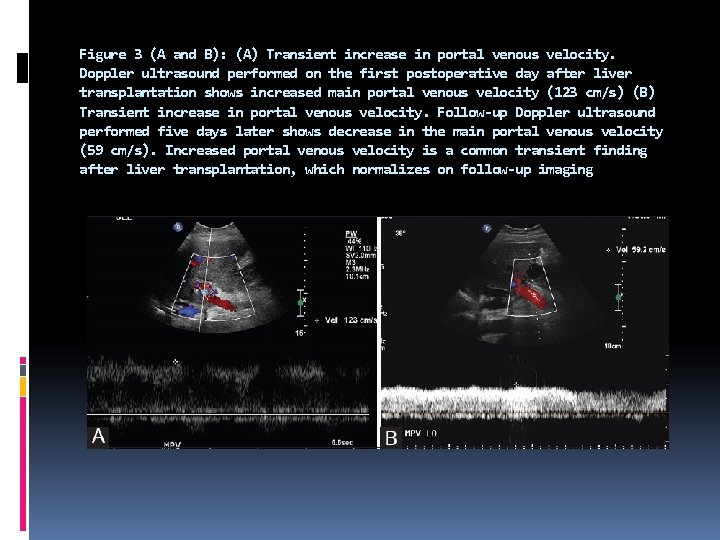

The reduction in portal venous resistance in the immediate post-transplant period can cause increased portal venous flow. This manifests as a high portal venous velocity, which gradually normalizes in the postoperative period, as the body adapts to the new hemodynamics. Compression of the portal vein by transient postoperative collections can also cause temporarily increased portal venous velocity, which normalizes as the postoperative fluid resolves.

A transient increase in portal venous velocity should not be misdiagnosed as portal venous stenosis, which is a rather rare complication. Hepatic veins normally have a triphasic waveform, but monophasic or biphasic waveforms are commonly seen in the postoperative period, secondary to graft edema or compression by the adjacent fluid collection. This usually normalizes on follow-up studies.

Figure 3 (A and B): (A) Transient increase in portal venous velocity. Doppler ultrasound performed on the first postoperative day after liver transplantation shows increased main portal venous velocity (123 cm/s) (B) Transient increase in portal venous velocity. Follow-up Doppler ultrasound performed five days later shows decrease in the main portal venous velocity (59 cm/s). Increased portal venous velocity is a common transient finding after liver transplantation, which normalizes on follow-up imaging